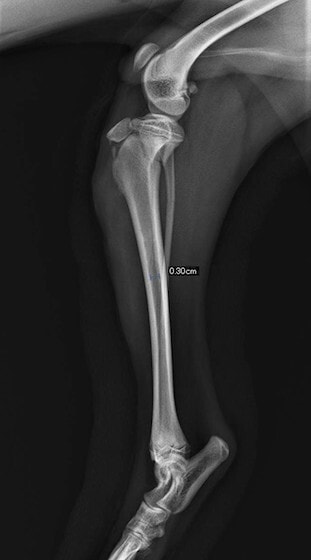

症例3:キルシュナーワイヤーのピンニングによる整復

ペルシャ猫 11ヶ月齢 雄

他院にて左大腿骨遠位の成長板骨折(salter-harrisⅠ型)が認められており、治療相談を目的として来院。当院にて、キルシュナーワイヤーを用いたピンニングにより骨折部位の整復を行いました。術後の経過は良好で、現在も経過観察中です。

術前レントゲン